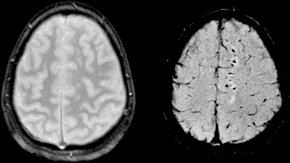

Image: Wikipedia